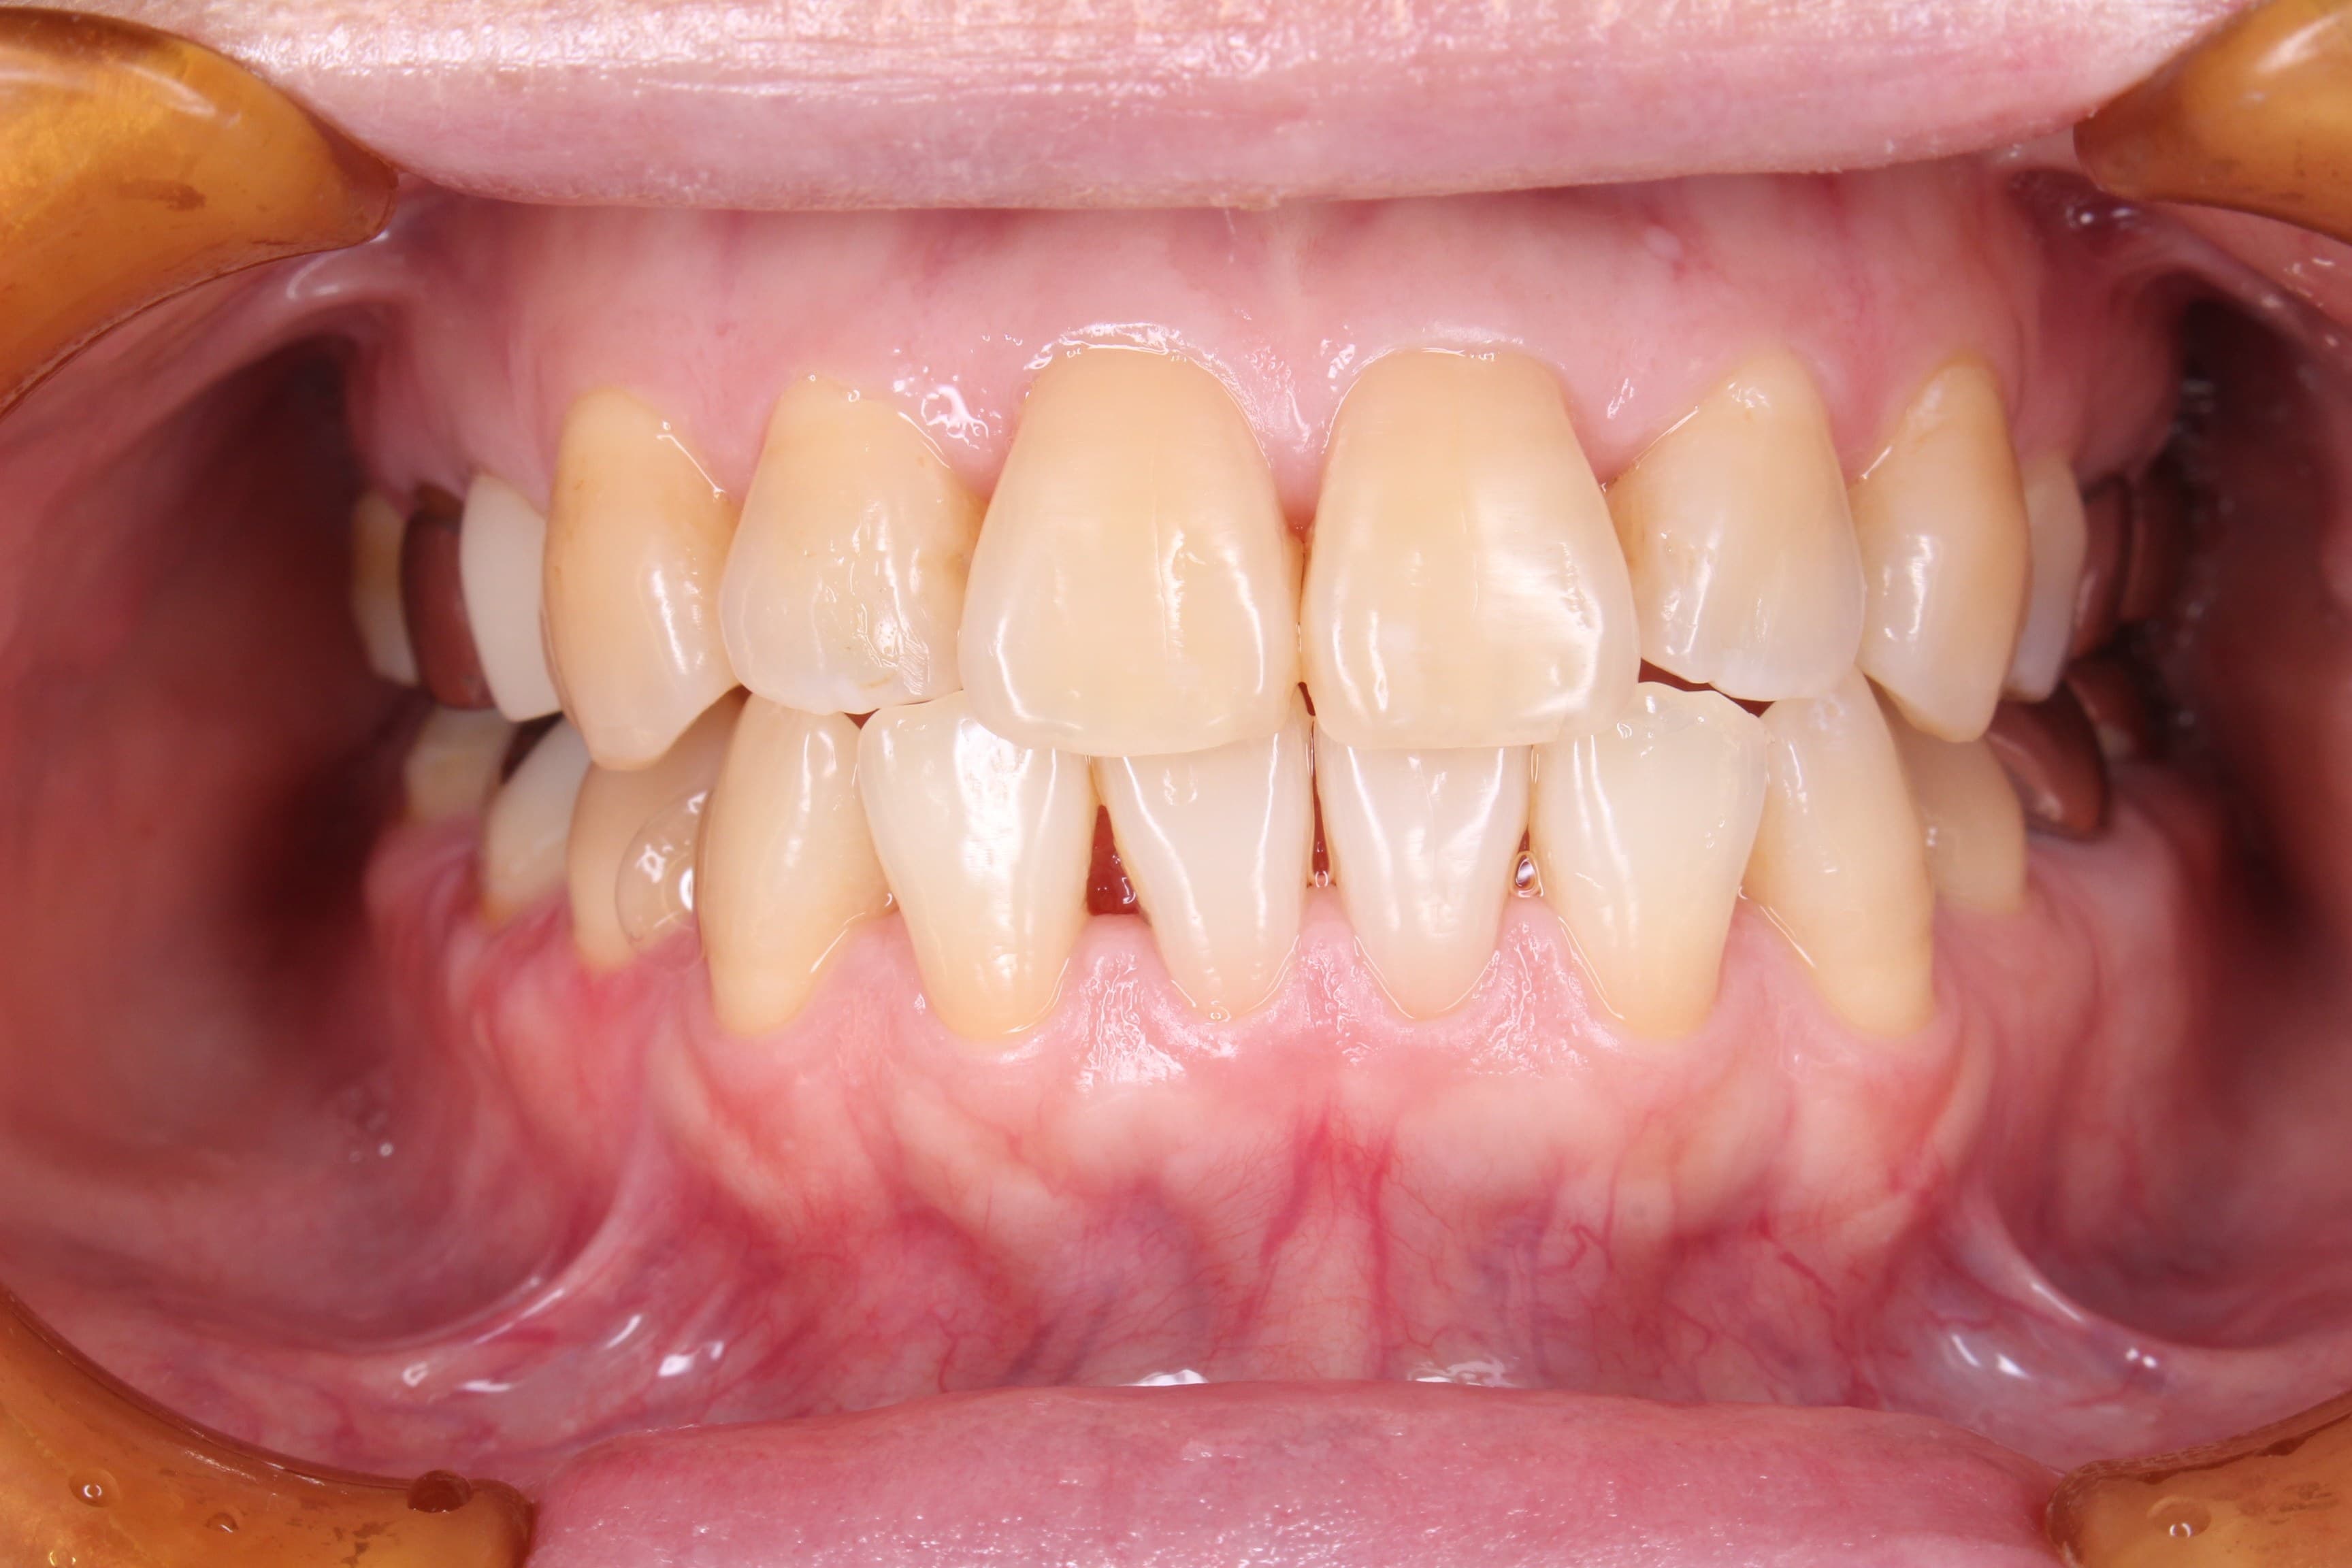

今回ご紹介する歯周専門治療のケースは、60代女性の方です。

50代から長期間身体を壊し、他院にて6か月に1度歯石取り(メンテナンス?)を行っていましたが、一向に口腔内のネバネバや不快感が改善しなかった為、来院されました。

基本検査の結果、全体的に中程度の歯周ポケットがあり、歯肉からの出血、歯周ポケット内に歯石を確認することができました。

またお手入れは、ご自身では見え難いところに磨き残しがありました。

治療前